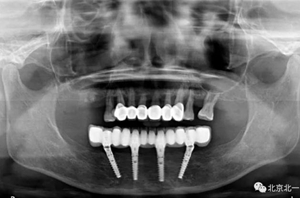

圖二十四:2017年11月復(fù)查時(shí)照片,植體很穩(wěn)定, 無骨吸收。

圖二十五:口內(nèi)照。